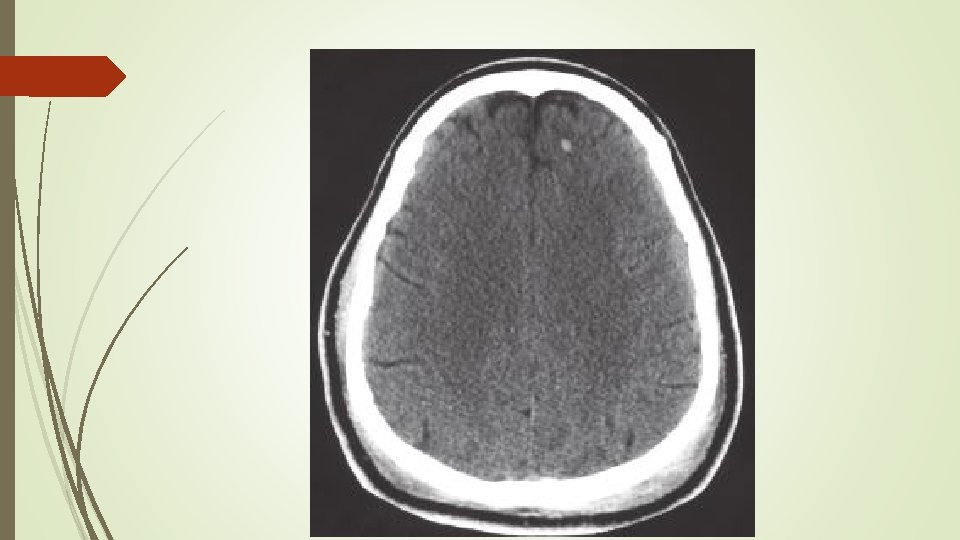

Özel kafa yaralanmalari Subdural hematom; § Köprü venlerin yırtılmasıyla meydana gelir. § Dura mater ile araknoid arasında hematom oluşumuna neden olur § Aşırı atrofik beyinler, yaşlılar ve alkolikler akut subdural hematoma daha yatkındır. § Akut (ilk 2 hafta) ve kronik (14. günden sonra) olabilir. § Akut subdural hematom BT de sütür hattını geçen hiperdens görünürken, kronik subdural hipodens görülür.